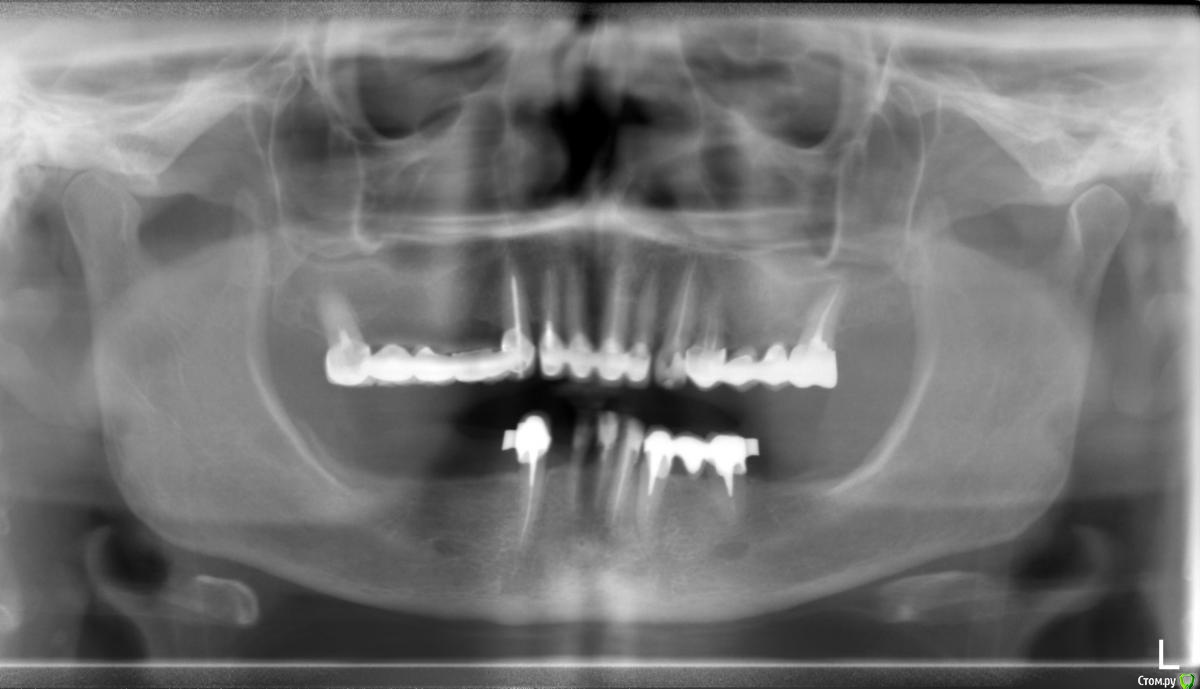

Dasha M Опубликовано 2 сентября, 2019 Поделиться Опубликовано 2 сентября, 2019 Добрый день. Собираюсь устанавливать импланты. В процессе поиска клиники нашла стоматолога с хорошими рекомендациями. Смутило то, что он получив мой снимок, сказал, что на нижней челюсти достаточно костной ткани и наращивания кости не потребуется. Те зубы, что отсутствуют на нижней челюсти, потеряны очень давно, лет 20 назад. Пожалуйста, помогите мне с ответом на 2 вопроса. 1. Достаточно ли костной ткани для имлантации. 2. Сколько имлантов лучше всего установить на нижней челюсти. Фото прилагаю. Большое спасибо! Ссылка на комментарий

Bier Опубликовано 2 сентября, 2019 Поделиться Опубликовано 2 сентября, 2019 Здравствуйте! По высоте костной ткани у вас достаточно, ширину на таком снимке не оценить, нужно либо смотреть во рту либо 3Д компьютерную томографию (CBCT) Минимум 3 штуки при условии сохранения оставшихся зубов. Ссылка на комментарий

колесников Опубликовано 4 сентября, 2019 Поделиться Опубликовано 4 сентября, 2019 5 имплантов и совершенно точно пластика десны (возможно дважды). О необходимости костной пластики-только после клкт (3д). Ссылка на комментарий